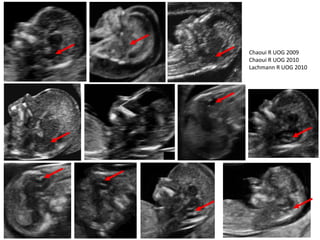

• 30 açık spina

bifidalı, 1000 normal

olgu.

• Geriye dönük

çalışma:

 Beyin sapı genişliği

artar (29/30).

 Beyin sapı-oksipital

kemik aralığı azalır

(26/30).

 Beyin sapı/beyin

sapı-oksipital kemik

oranı artar (30/30).

Lachmann R Prenat Diag 2010

Gelişen USG görüntüleme teknolojisiyle ilk üç ayda da

arka kafa boşluğunun değerlendirilmesi mümkün olmaya

başlamıştır.

Chaoui R UOG 2009

Chaoui R UOG 2010

Lachmann R UOG 2010